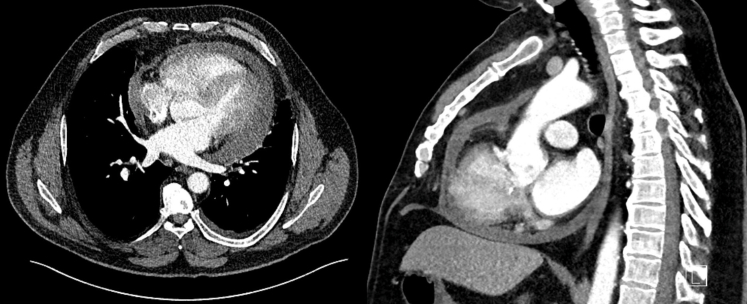

At day 11 after ablation, the patient re-presented with symptoms of general malaise and fevers with rigors and night sweats. The CRP was now 138 mg/L. There was now a significantly increased circumferential pericardial effusion at 1.6 cm maximum depth without echocardiographic features of tamponade. He was admitted to the cardiology ward and the suspicion of esophagopericardial fistula prompted a cardiac gated computed tomography scan of the thorax (Figure 1). This revealed a moderate-sized pericardial effusion and a small left-sided pleural effusion but no evidence to support cardiac perforation or atrioesophageal fistula. Respiratory polymerase chain reaction swabs did not detect any pathogen. Urinalysis and microscopy were negative. Blood cultures were negative for any growth.

Figure 1.

Top: Transverse plane image of contrast-enhanced computed tomography showing moderate circumferential pericardial effusion measuring 15–30 Hounsfield units. There is a small left-sided pleural effusion also seen. No evidence of contrast extravasation was demonstrated. Bottom: A sagittal plan image showing circumferential pericardial effusion, contrast in the left atrium, and no demonstrable communication with the esophagus.